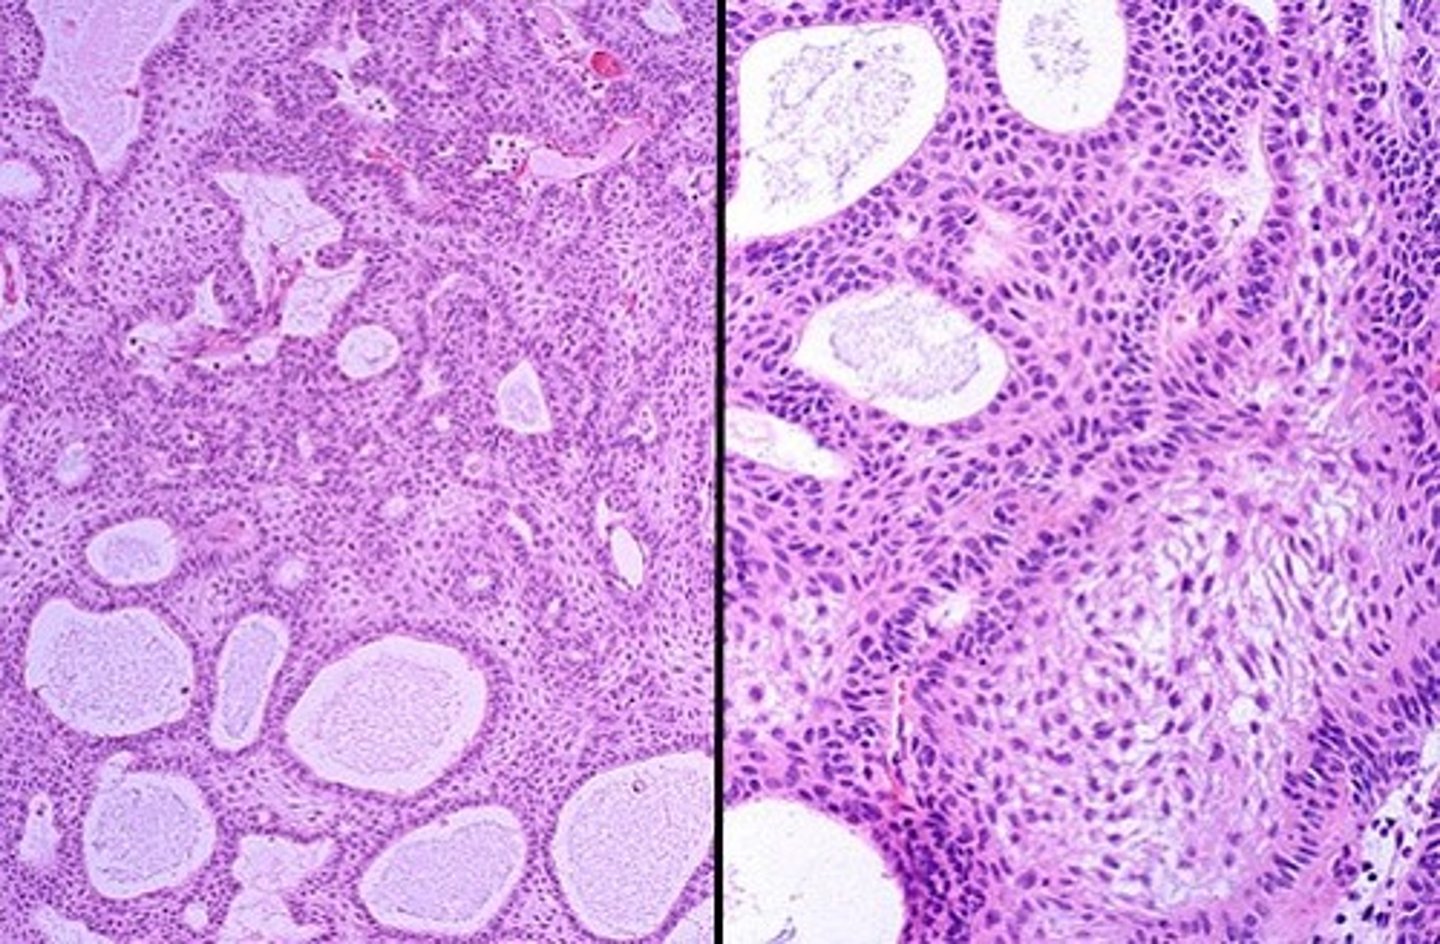

Adamantinomatous craniopharyngioma

CPH tumor type that occurs mostly in children

lobulated spongy mass that usually contains cystic spaces

gross pathology of Adamantinomatous craniopharyngioma

what type of CPH?

-nests of stratified squamouss epithelim

-top layer forms wet keratin which is heavily calcified

-basal layer

-inermediate layerr of reticulum

-top layer--> wet keratin

layers of the nests in Adamantinomatous craniopharyngioma

Papillary craniopharyngioma

CPH with fibrovasculuar core covered by mature squamous epithelium